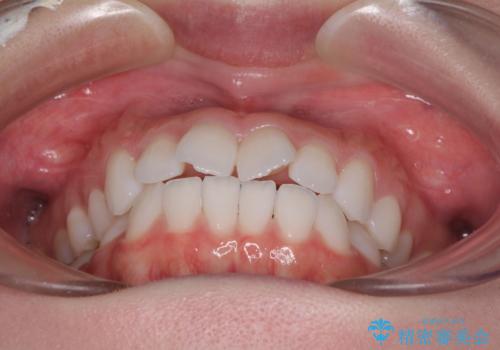

- 海外留学を前に上下のデコボコと奥歯の咬み合わせを改善したいとのことで来院された患者様です。

期間が限られていたため、ワイヤー装置による矯正治療を行うこととしました。

治療開始から4ヶ月ほどで概ね歯列が整い、その後の3ヶ月で細かい部分を仕上げていきました。

短期間で綺麗に仕上がり、患者様には大変満足していただきました。